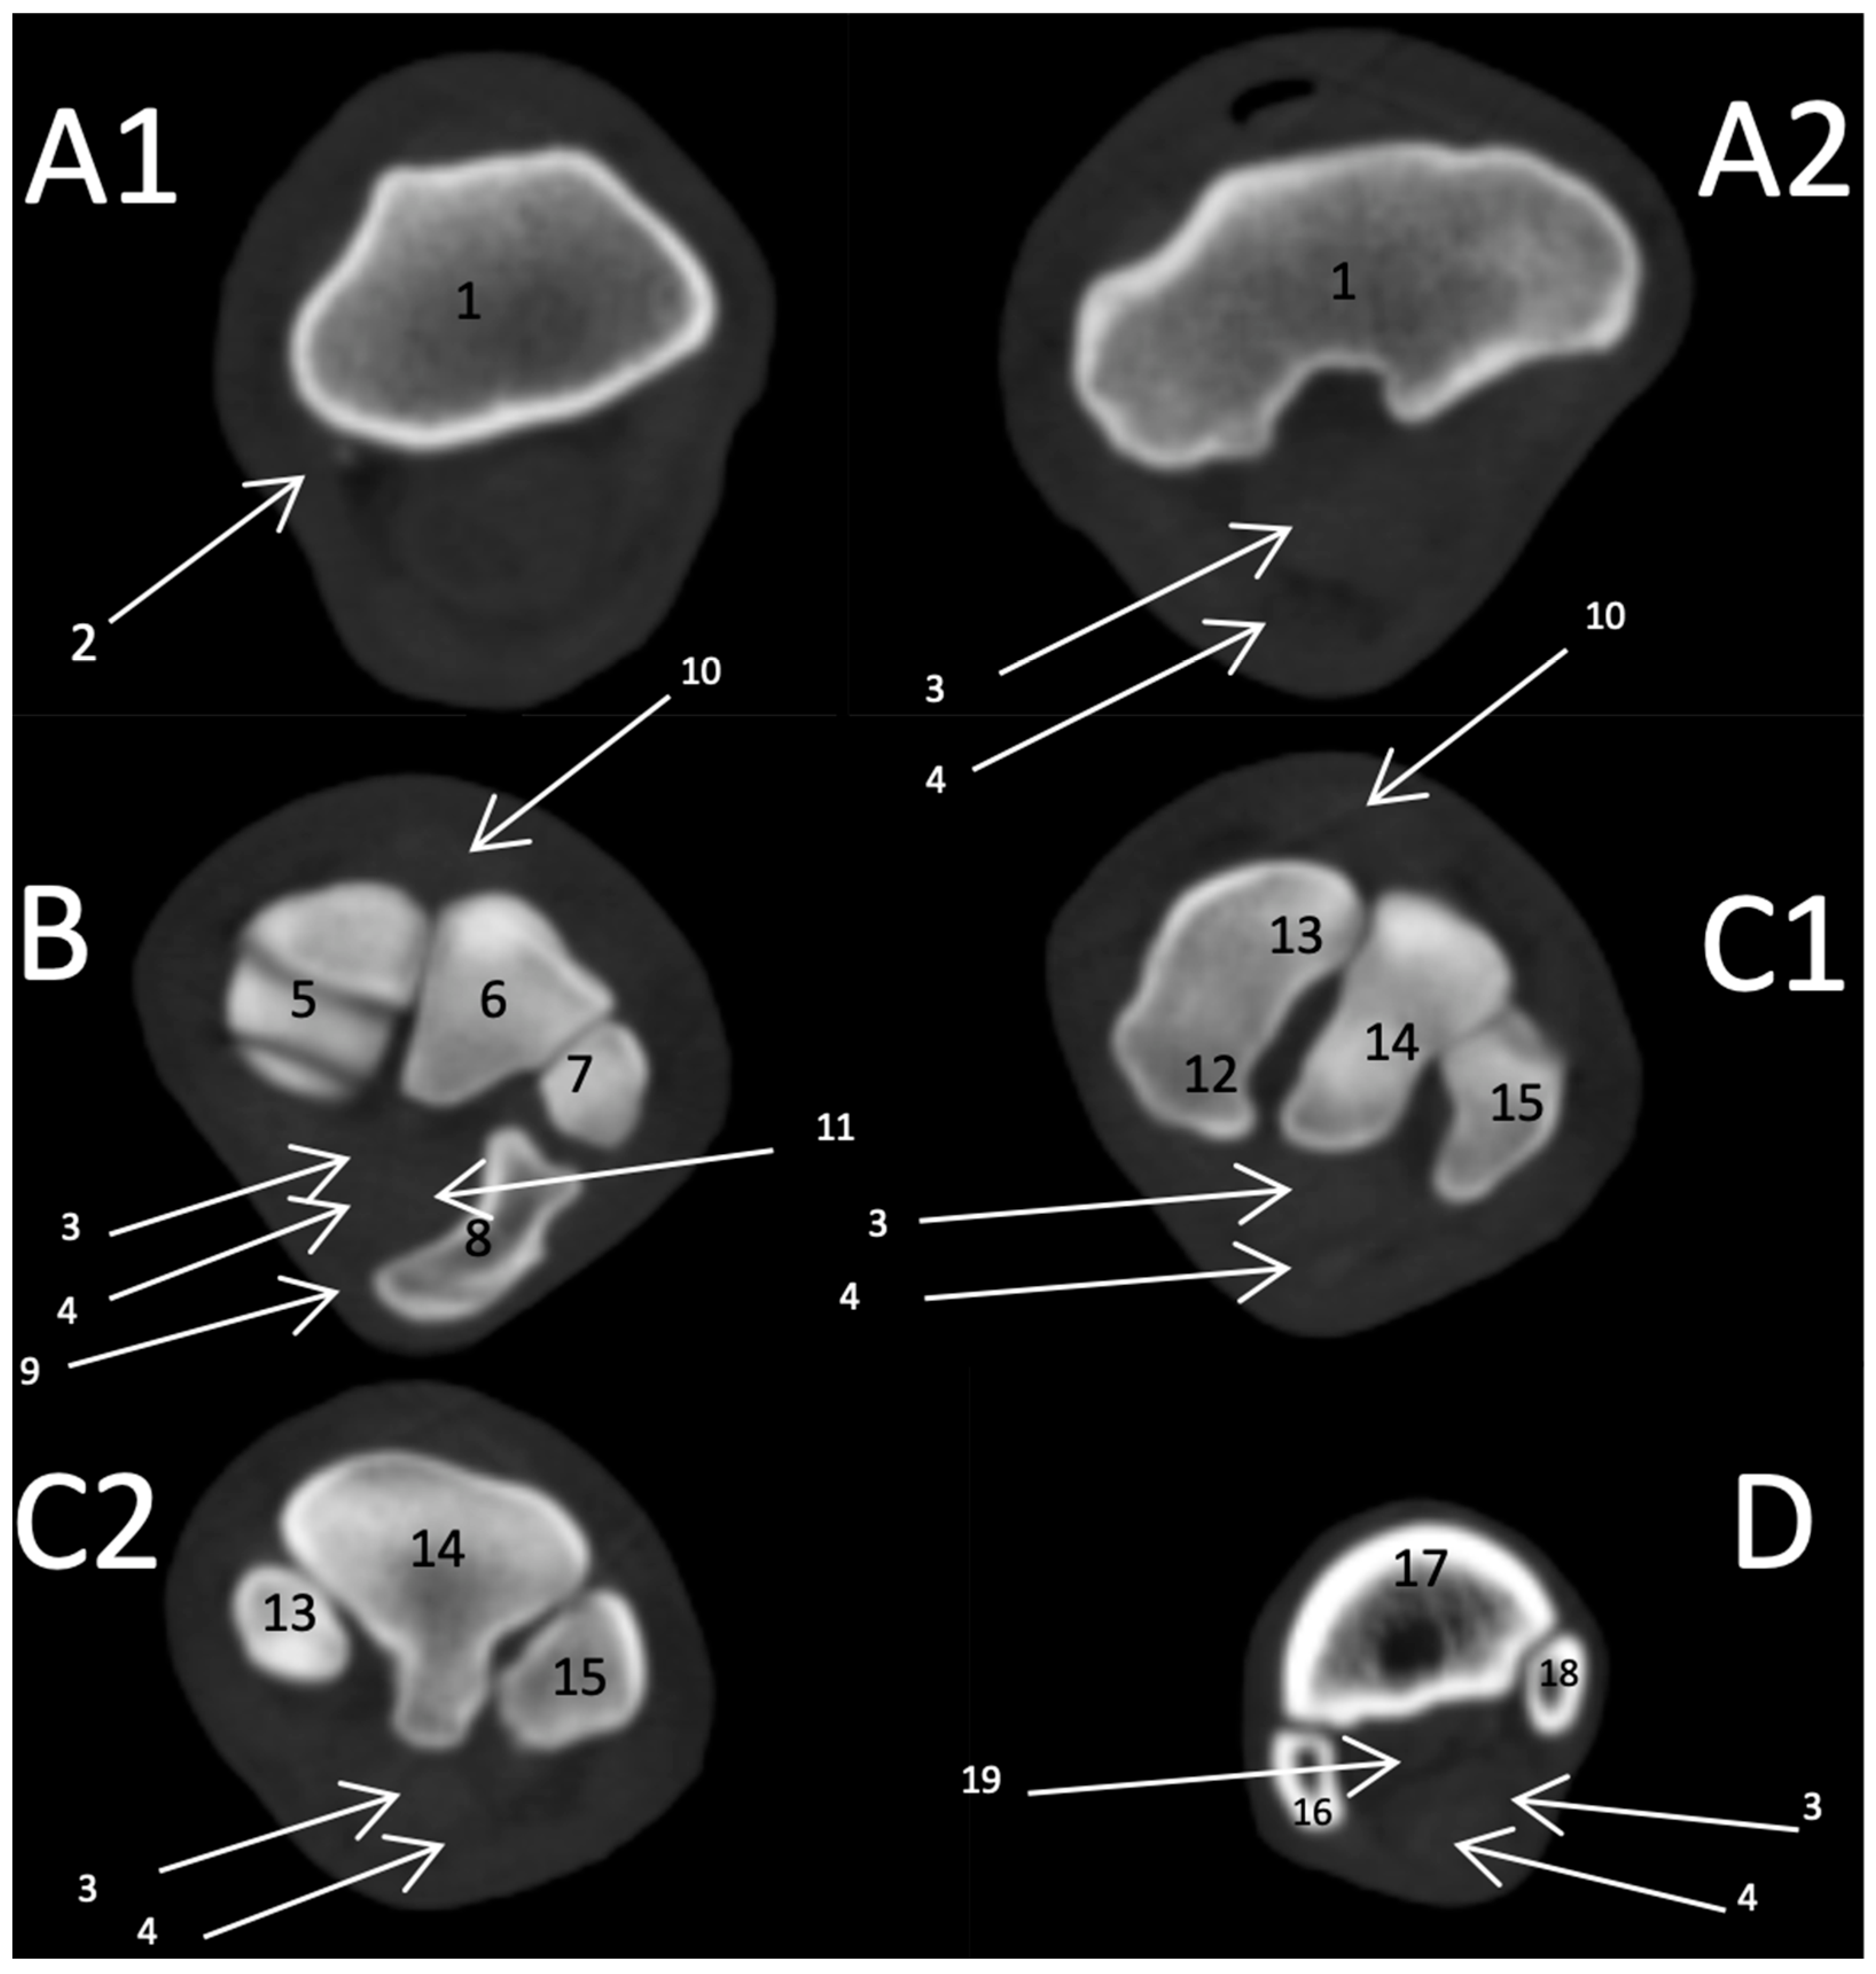

3.2.2. Transverse Scan